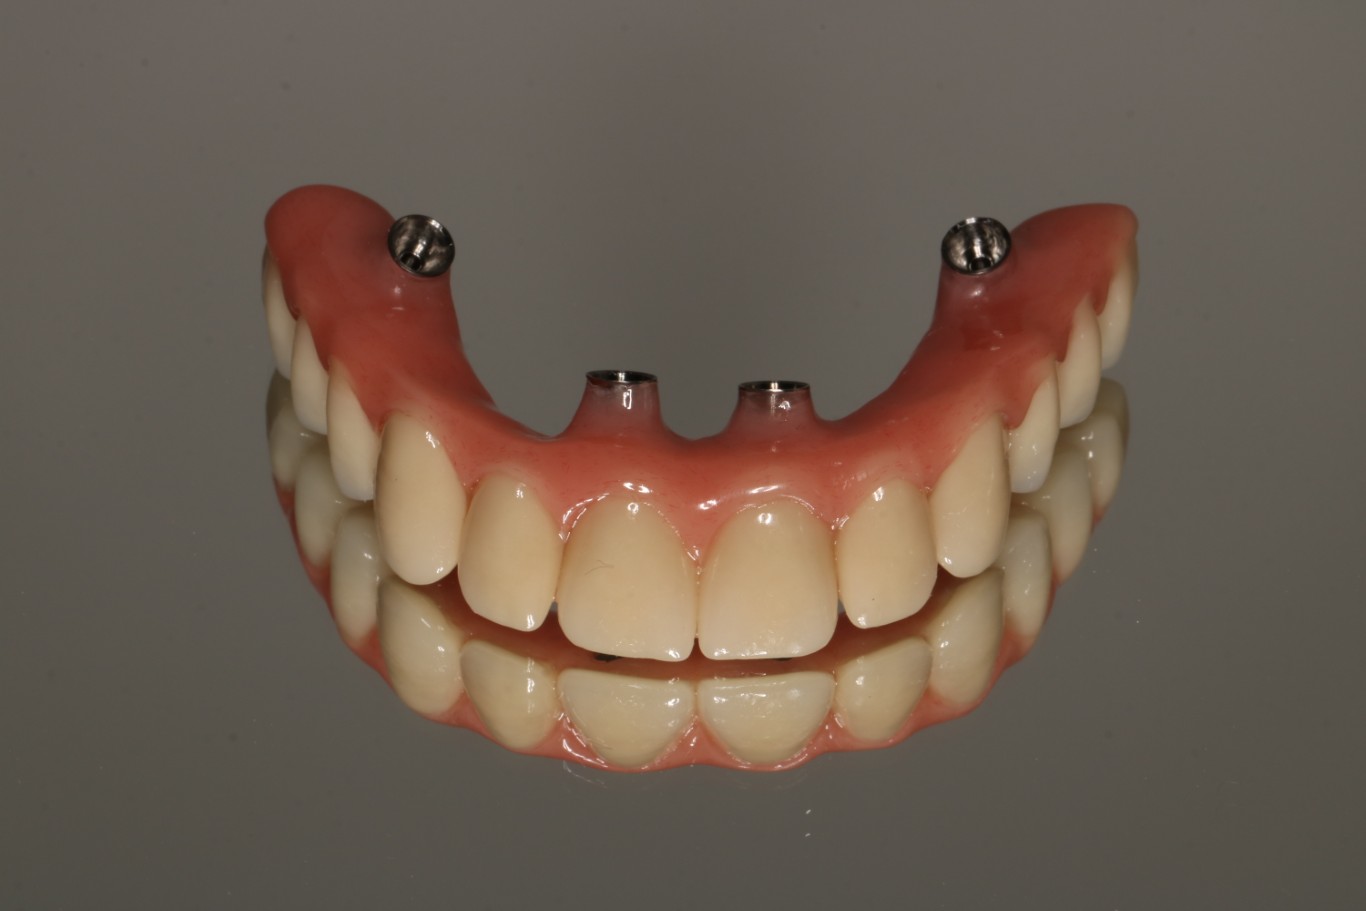

1. Proteza wykonana wg protokołu All On X

Metoda All On X to rewolucyjne podejście do odbudowy całej szczęki na implantach. Polega na osadzeniu pełnej protezy stałej na odpowiedniej liczbie implantów (zwykle 4-6), strategicznie rozmieszczonych w kości szczęki lub żuchwy. Liczba implantów jest dobierana indywidualnie do każdego pacjenta – stąd nazwa “All On X”, gdzie X oznacza optymalną dla danego przypadku liczbę wszczepów.

Proteza wykonana w technice All On X może przez długi okres funkcjonować jako uzupełnienie samodzielne i jest najczęściej wstępem do wykonania stałych uzupełnień protetycznych np. mostów porcelanowych przykręcanych dna implantów